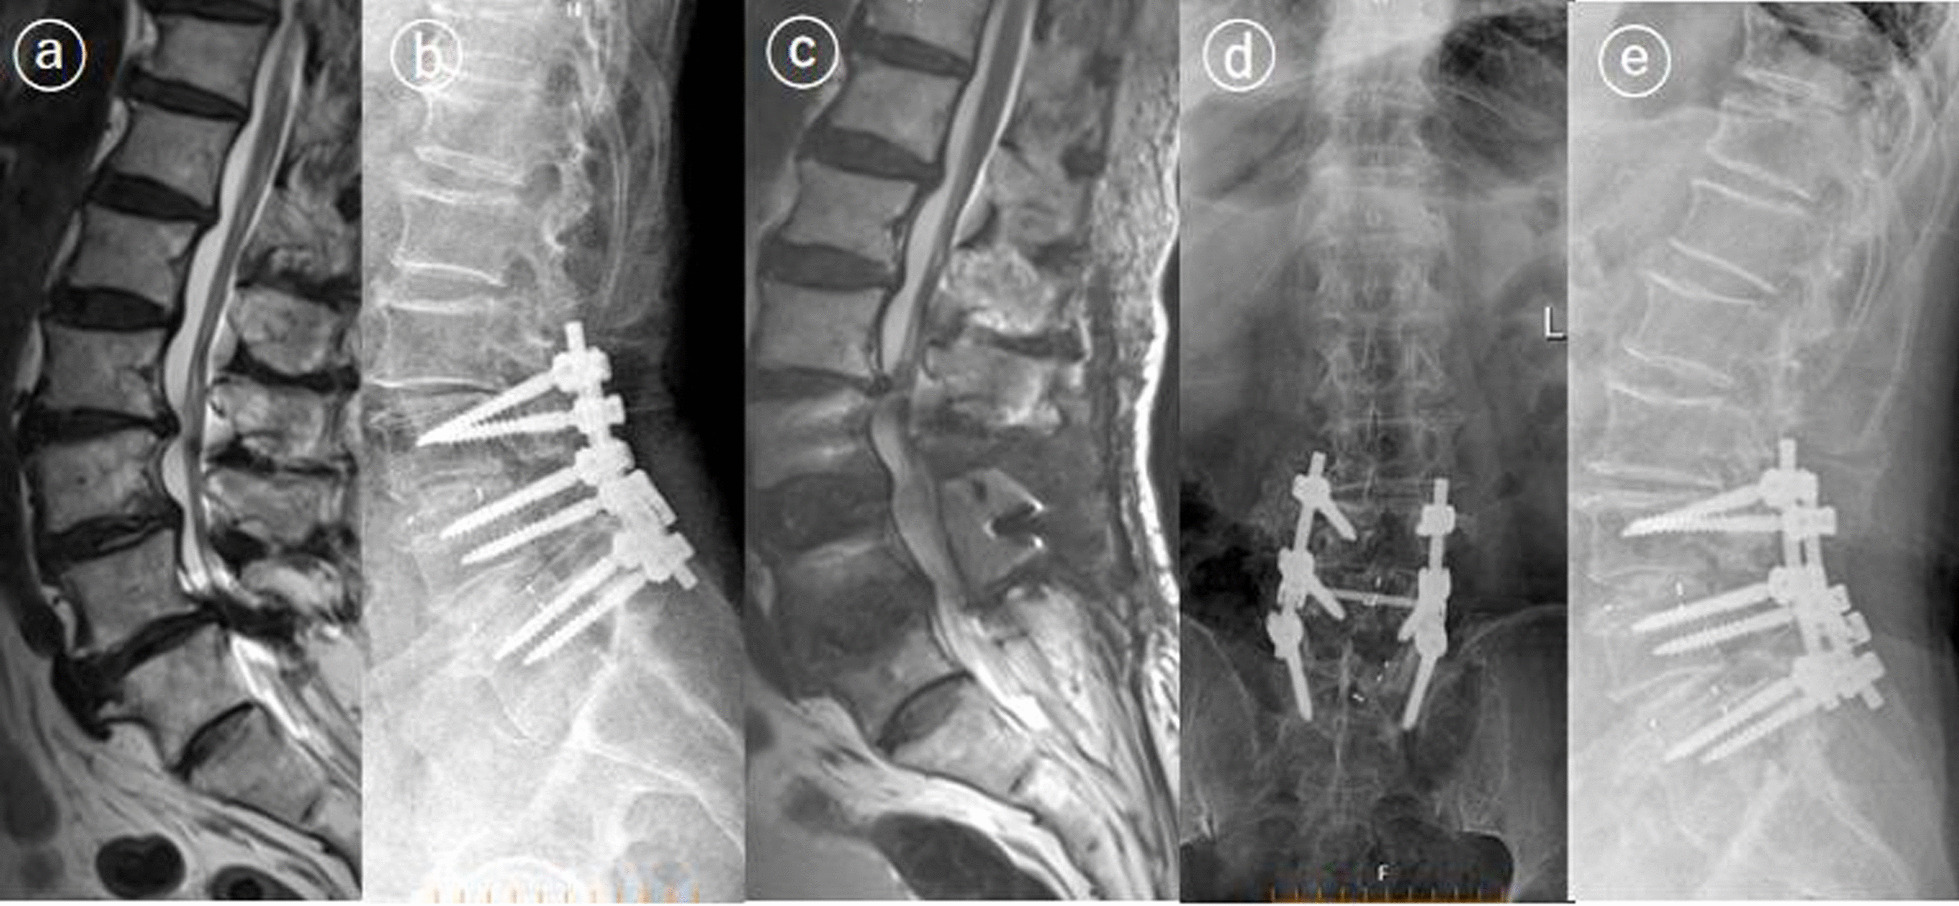

Fig. 2.

A 57-year-old patient underwent second surgery for persistent pain. The patient underwent decompression and posterior L3–L5 fusion surgery for lumbar spondylolisthesis and lumbar spinal stenosis (a–c). Preoperative leg pain was not adequately relieved after the first operation and lumbar spine MRI revealed residual stenosis at L2–L3 and L3–L4 (c). After adequate decompression surgery, the patient’s pain was relieved (d, e)